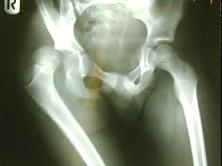

问题 男,44岁,因外伤右髋痛12小时。查体:生命体征平稳,右下肢短缩,髋关节屈曲,内收,内旋畸形。请结合所提供的图像,进行选择: 应选择的治疗方法 ( )

选项 A、Braun架 B、Thomas架 C、Knowles针 D、Ender杆 E、Allis法

答案 E